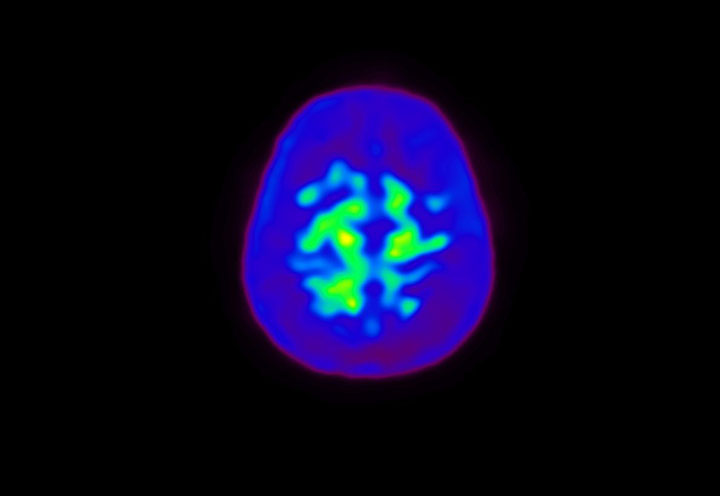

Head / Case4 : Amyloid

Axial

Courtesy : Kindai University Hospital

- Injected dose: 3.21 MBq/kg, 18F-Flutemetamol

- Uptake time: 100 minutes

- Scan time: 20 minutes